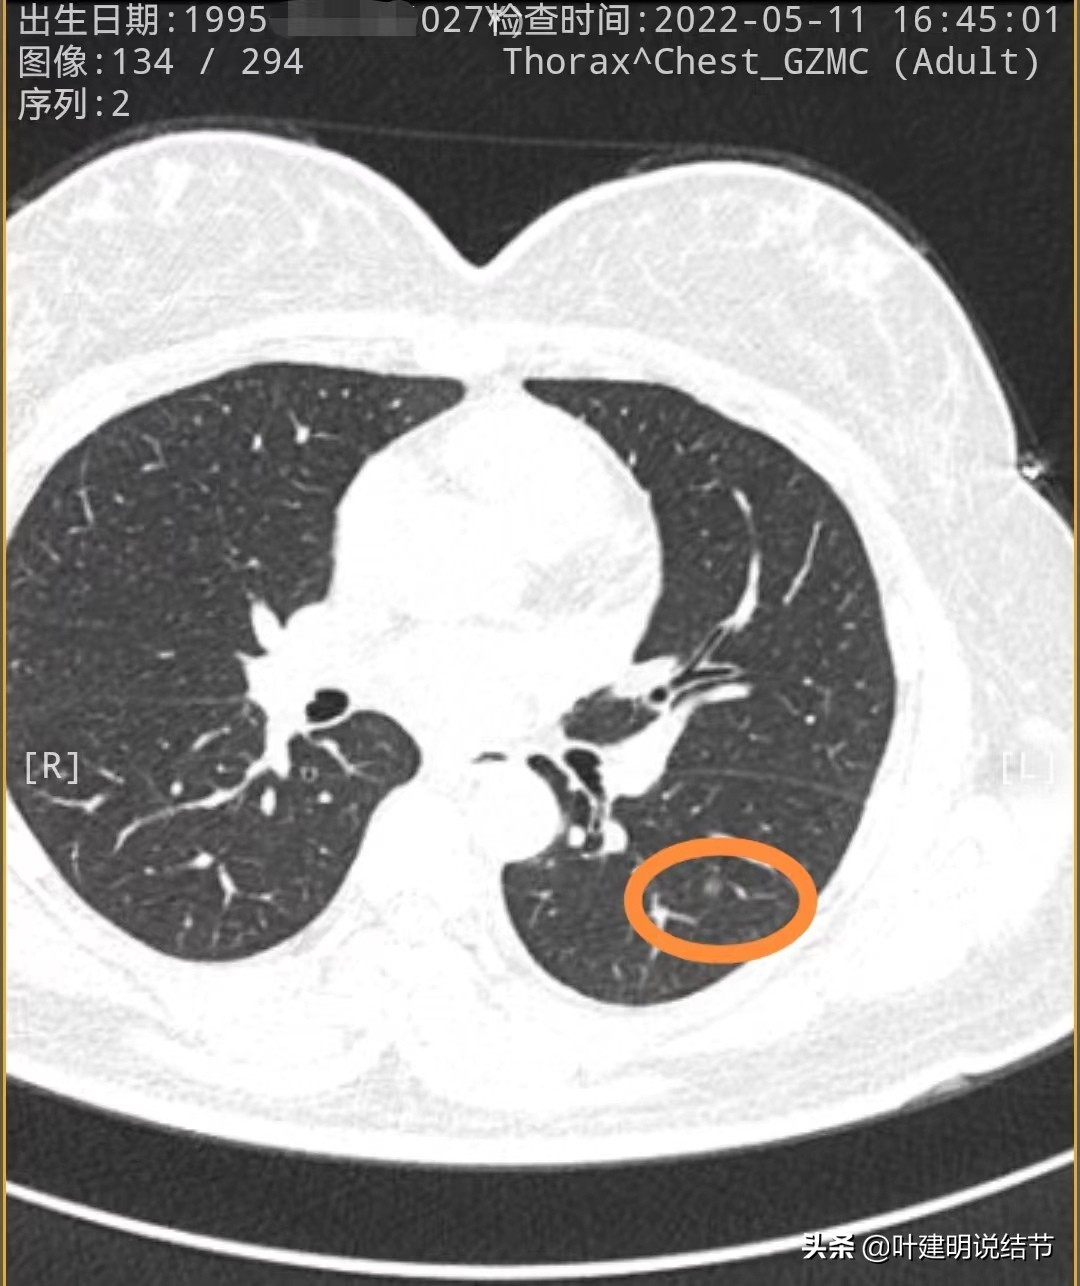

再来看今年2022年的片子:

左下第一处结节几乎没有明显变化

左上舌段结节感觉略圆起来一点,但大小说不上显著增大进展,轮廓清

左下另一处结节感觉略有进展,但总体应该仍是原位癌可能性大些。